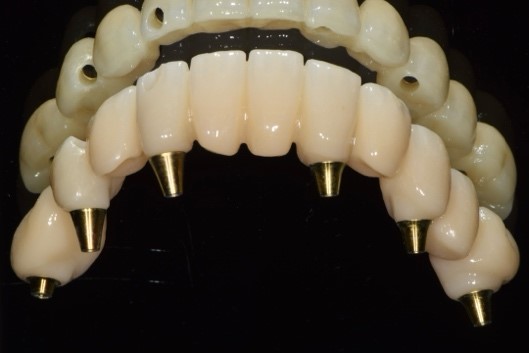

Il laboratorio odontotecnico utilizzava le più recenti tecnologie CAD/CAM per produrre una protesi dentale personalizzata e di alta qualità che si adattasse perfettamente e garantisse funzionalità ed estetica ottimali. Il concetto iPhysio® facilita il recupero automatico del profilo di emergenza sottogengivale da parte dell'odontotecnico per la realizzazione di soluzioni personalizzate sia con la protesi cementata che con la protesi avvitata (Fig. 5 a,b,c). La paziente tornava per il posizionamento del restauro finale in zirconio avvitato (Fig. 6 a,b).

Profili di emergenza ideali disegnati dagli iPhysio

Fig. 5(a)

Profili di emergenza ideali disegnati dagli iPhysio 2

Fig. 5(b)

Profili di emergenza ideali disegnati dagli iPhysio 3

Fig. 5(c) Profili di emergenza ideali disegnati dagli iPhysio®.